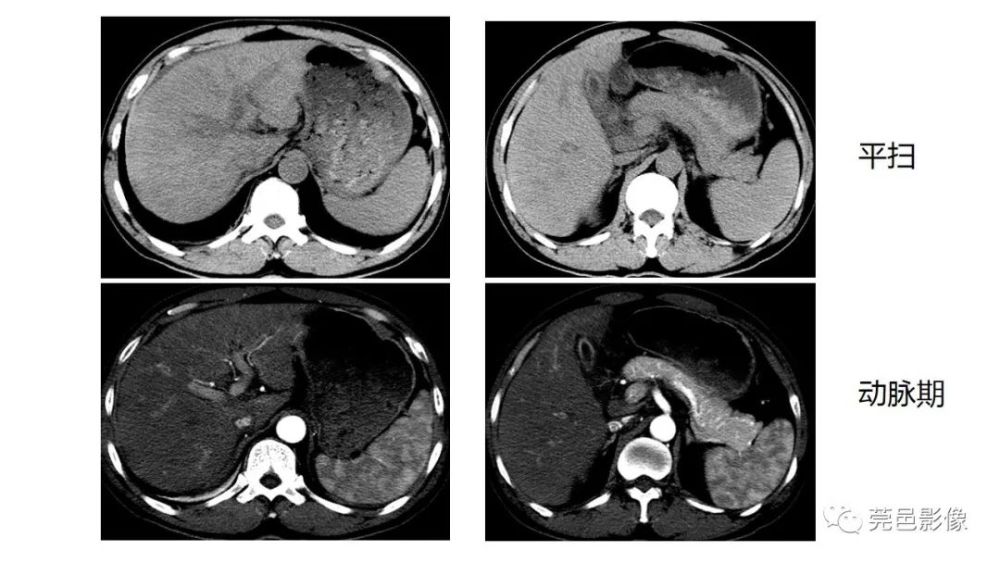

【讨论】膈下积液和肝包膜下积液您区分的开吗

图2c肝脏成扇贝样改变(肝脏由于受肿瘤实质性或囊性组织压迫而其实质